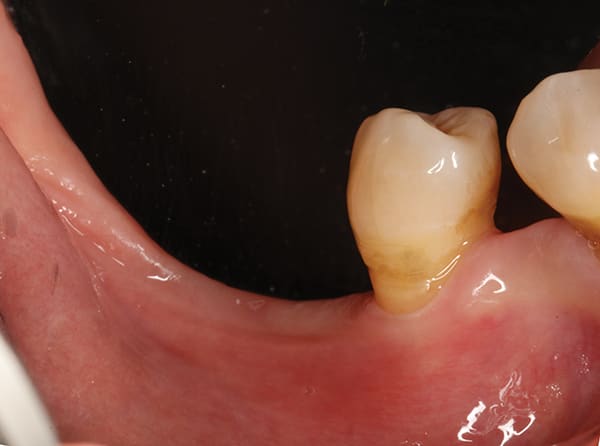

Severe Crestal Atrophy

The patient presented with the posterior mandible showing severe atrophy (Figure 16). The computed tomography (CT) scan showed 3.6 mm and 4.6 mm of available bone height with a failing premolar (Figure 17 and Figure 18). To regain function, the premolar was removed, and two Ultra-Short implants were placed in the molar region and splinted together (Figure 19 through Figure 22).